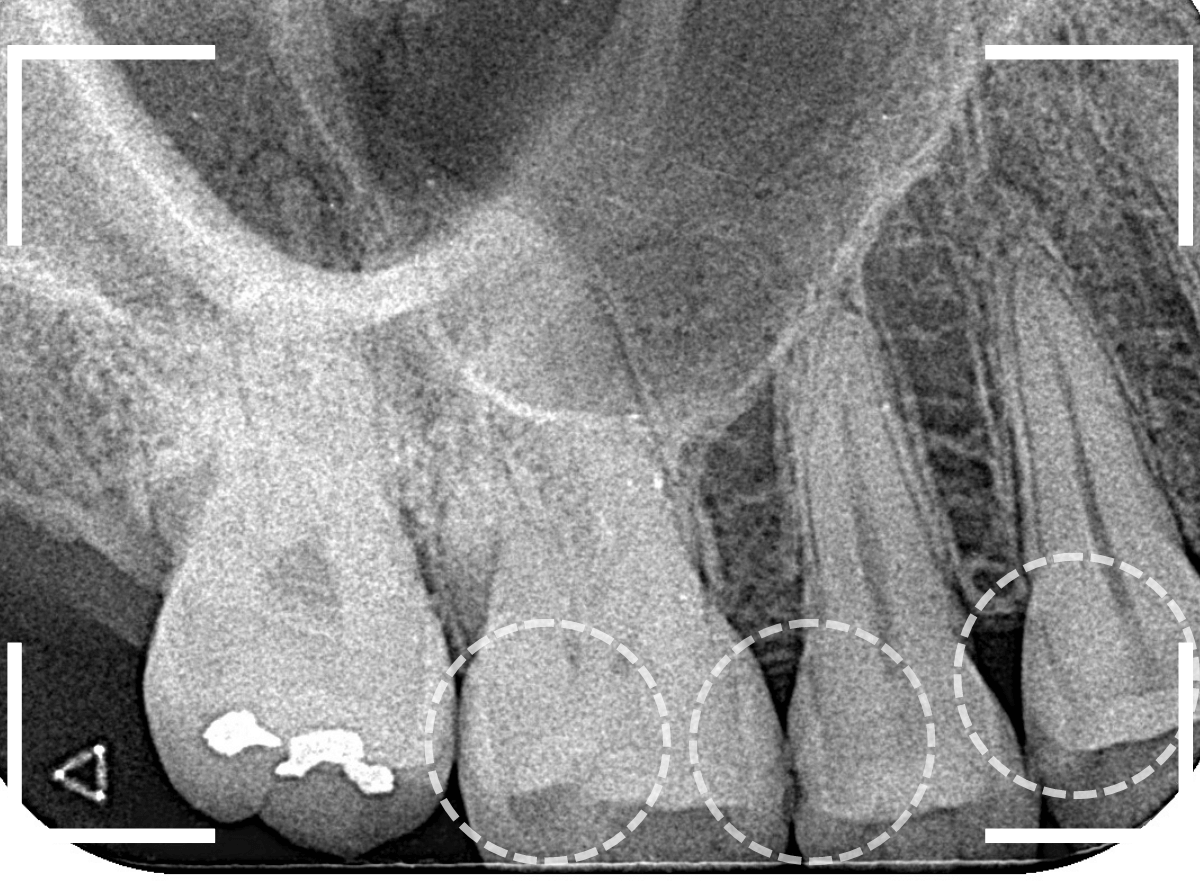

Case.10 レントゲンに写らない側面の虫歯を、少しずつ削って調べる

こちらも、虫歯が歯のあちこちで進行してしまっている患者さんのケースです。

特に側面の虫歯が深そうです。

側面にできた虫歯はレントゲン写真では診断しづらくやっかいです。

今回は「見るからに深そう」ですが。

さすがにレントゲン写真でも虫歯がありそうな事は確認できますが、実際にどうなってるのかはあまりはっきりわかりません。

少しずつ虫歯を除去していきます。

歯の側面から、手前の歯までつながった虫歯になっていました。

手前の歯までの虫歯を除去しました。

歯の後ろ側の側面も、大きな虫歯になっていますので、処置します。

隣の歯との間(隣接面)は、中で虫歯が広く進んでることが多いです。

結局、前後の歯に渡る広い虫歯でした。

レントゲン写真だけでは、ここまでの虫歯は判断できませんでした。